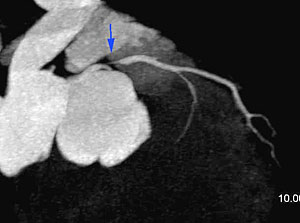

This patient, with a strong family history, had an episode of chest pain a month ago with an equivocal stress test. The cardiac CT (A, B) shows a severe stenotic lesion in the proximal LAD (blue arrows), which was confirmed on the catheter angiogram (C) and the patient was successfully stented.